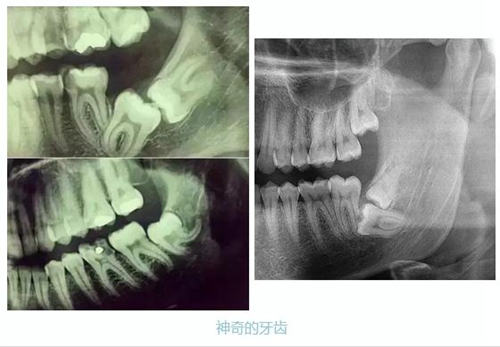

先放幾張圖,讓你們漲漲姿勢,不拍片根本不知道你的牙齒長得會有多奇葩!

牙齒的牙根是埋在牙槽骨中的,醫(yī)生沒有透視眼,為了解患牙的牙根的形態(tài)、走向、長度及根尖周有無病變及病變大小,或者懷疑有肉眼無法確認的其它牙科問題,都會建議患者去牙科的X光,甚至,口腔CT來全面性地確認問題,以訂定合適的治療計劃。